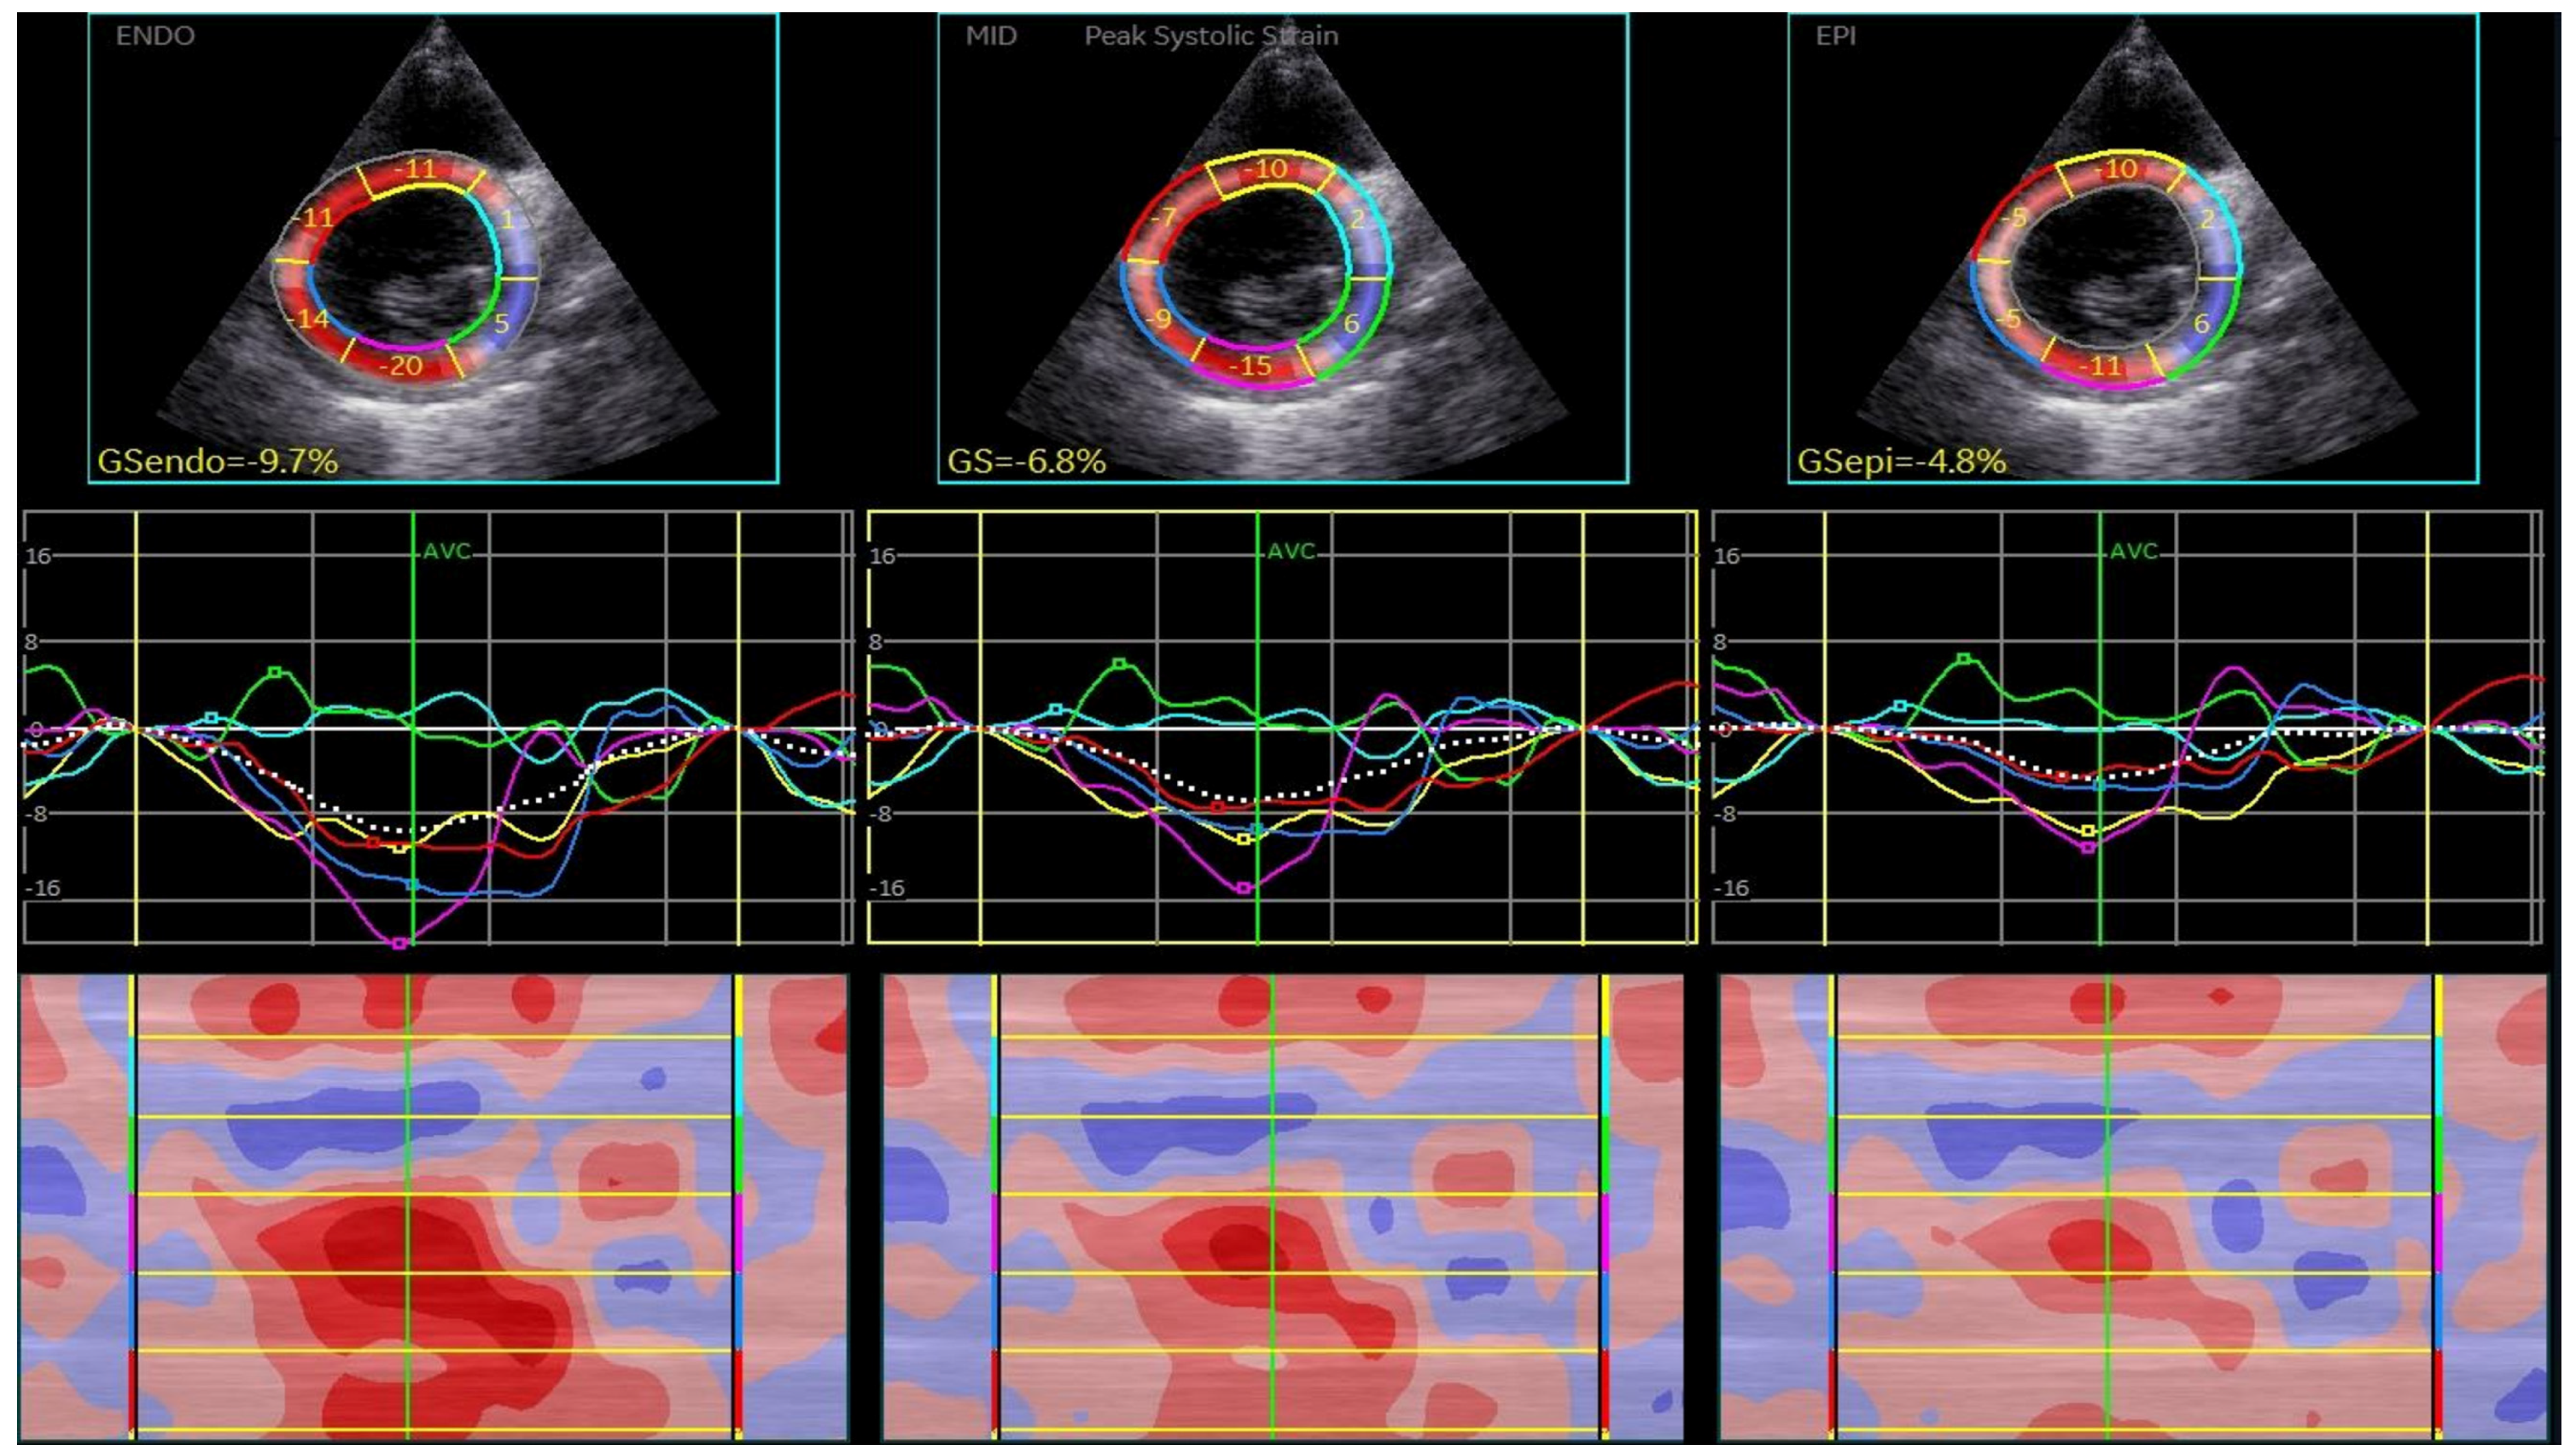

2.2.2. Two-Dimensional Speckle-Tracking Echocardiography

3.2. 2D Speckle-Tracking Echocardiography Results